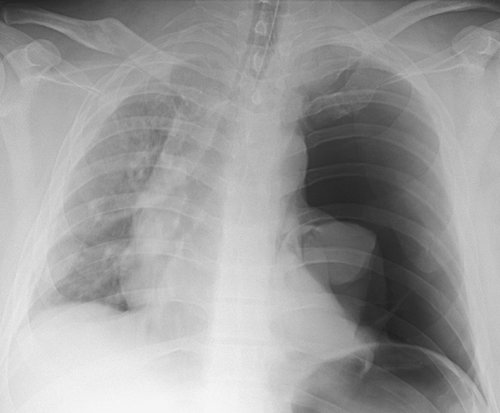

FIGURE 9-12. Re-expansion pulmonary edema. A: PA chest radiograph of a 78-year-old woman with metastatic breast cancer shows a large left pleural effusion associated with collapse of the left lung and shift of the mediastinum to the right. These findings suggest tension hydrothorax. B: PA chest radiograph after placement of a left chest tube and adequate drainage of pleural fluid shows re-expansion pulmonary edema on the left.